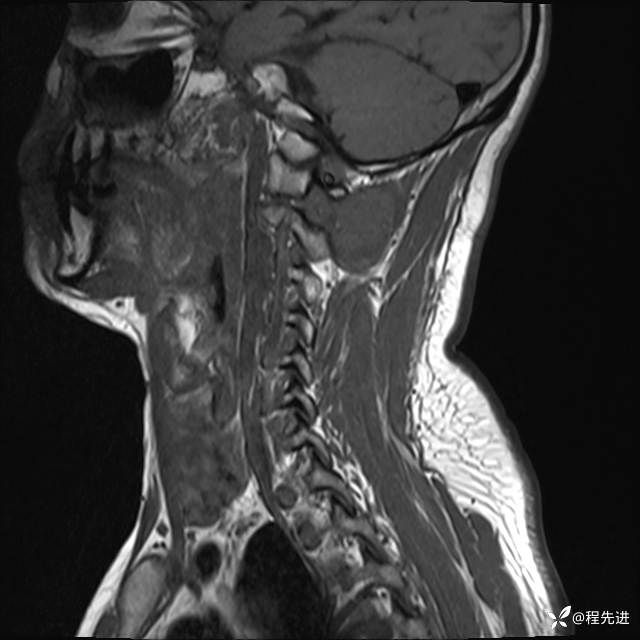

MRI平扫+增强:

T2:

T1: